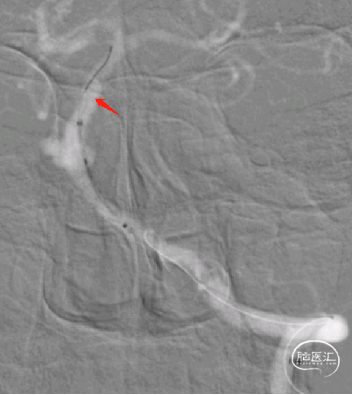

术后影像:

术后3月余复查:

动脉瘤愈合,支架内血流通畅。